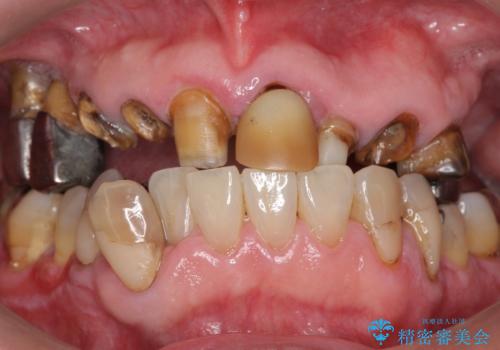

- 前歯の被せ物がとれたまま放置されていた患者様です。

前歯4本のうち3本の被せ物が脱離し、残りの1本の被せ物は劣化し変色していました。

古い被せ物や土台・虫歯をしっかり除去したのち、セラミック治療を行いました。

患者様のご希望により、根尖病変の明らかな左上2のみ根管治療を行いました。

- ¥610,000 (根管治療×1本、土台×4本、仮歯×4本、クラウン×4本)費用は治療当時の料金となります